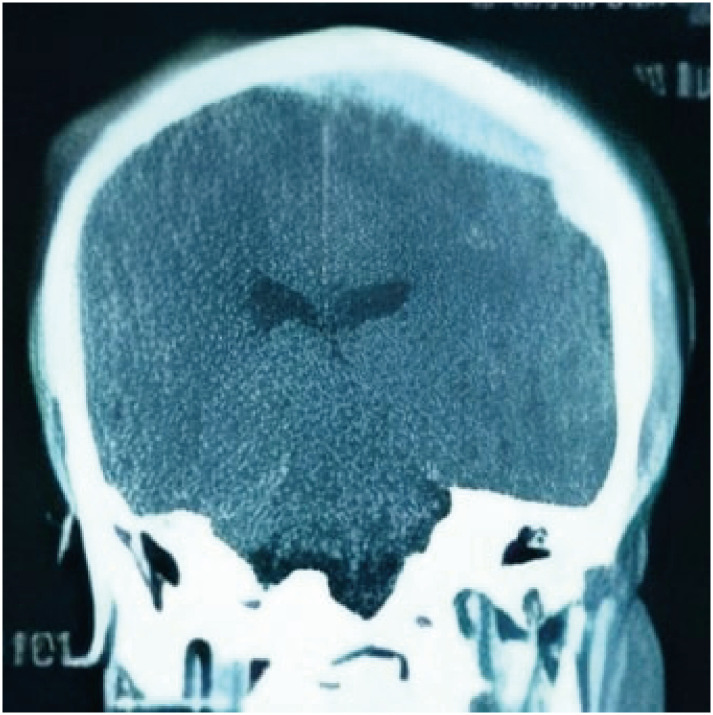

Vertex epidural hematomas are very uncommon complications of traumatic head injury. Besides the volume of the epidural bleeding, compression of the superior sagittal sinus may be source for added elevated intracranial pressure. Clinical presentation of such lesions is heterogenous and symptoms can develop in an acute to a chronic frame. Radiological diagnosis can sometimes be challenging. Due to its rarity, such lesions have been only reported on case reports and small series and the management remain controversial. Hereby we report 3 cases of surgically managed post traumatic acute epidural hematomas of the vertex. Wen also went through a literature-based discussion of clinical, radiological and therapeutic features related to this condition.

Abstract Image